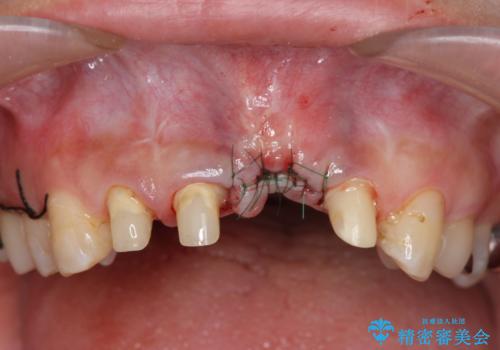

左側の前歯には他院で埋入されたポジションの悪いインプラント補綴により歯冠長の長いクラウンが装着されており、感染による排膿も認められこのまま審美性を改善するのは難しい状態です。

不良インプラントを除去し最終的にブリッジによる補綴で審美性の改善を行うこと、その準備として骨の造成・歯肉の移植による歯の欠損部顎堤のボリュームを維持・増大を計画します。

感染したインプラントからは排膿が間欠的に認められ、掻爬・除去が検討されうるような状況でした。

より審美的な改善を強く求められたため、インプラントを除去し可及的に欠損部顎堤を増大したのちブリッジによる審美改善を行いました。